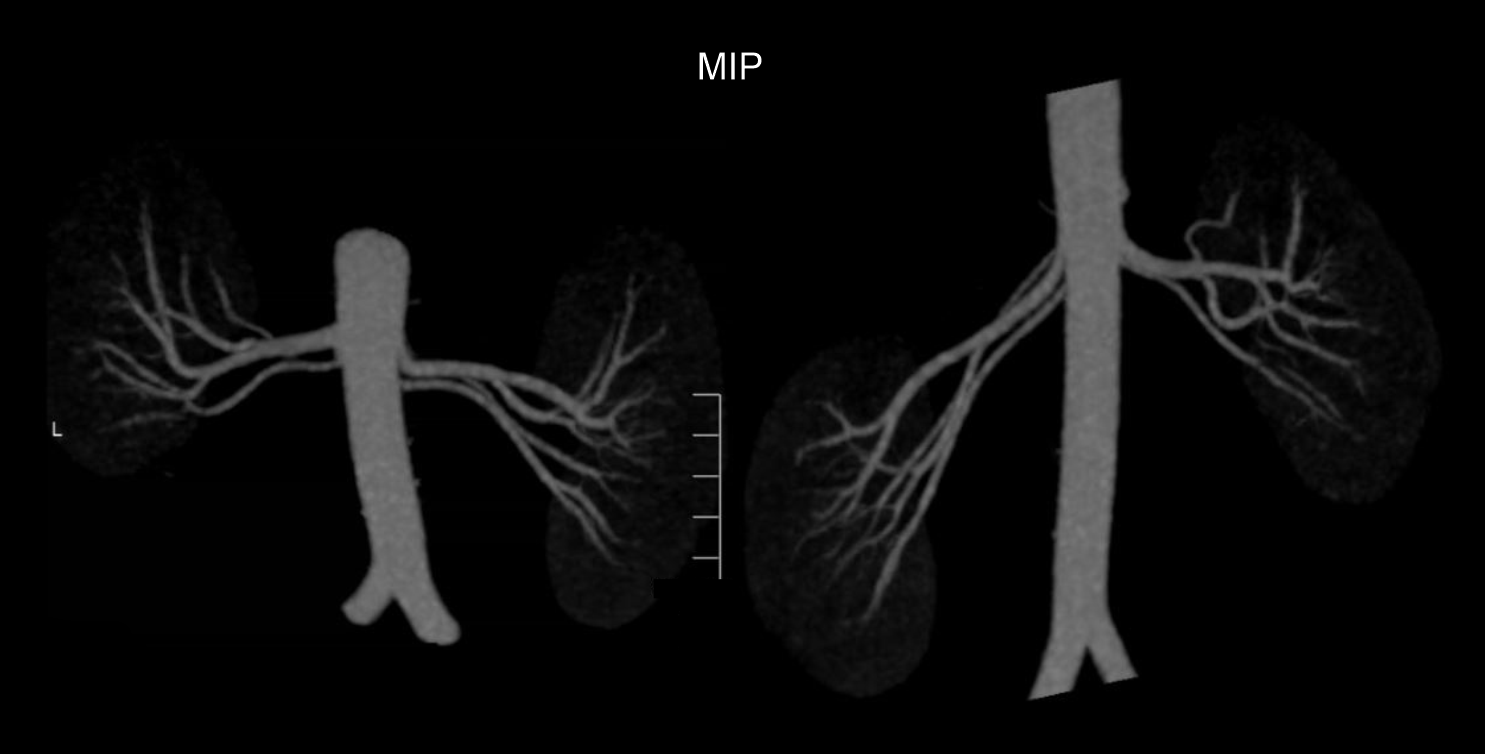

- MIP images through the kidneys to show small accessory renal arteries.

- Curved MPR images of nephrographic phase to show renal venous system and distance from inferior vena cava (IVC) margin to venous bifurcation.

- 3D, MIP, curved MPR images from excretory phase to show ureters.